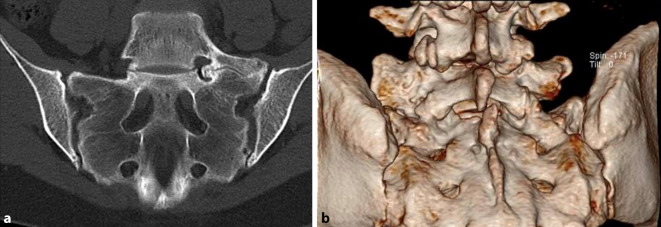

Background: Lumbosacral transitional vertebrae (LSTV) are common, with a prevalence of 15-35%, and can be a cause of specific low back pain. The insufficient awareness of this anomaly often leads to delayed diagnosis and treatment.

Results: Patients with symptomatic Bertolotti syndrome often suffer from chronic low back pain and radiculopathies. Imaging techniques, particularly X‑rays and MRI, play a key role in diagnosis. Conservative treatments show limited success. Surgical resection of the transverse process (processectomy), especially after positive test infiltrations, leads to significant pain relief, particularly in younger patients without degenerative changes.